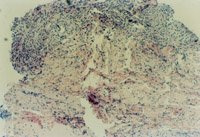

3-17 È¡ÉÕÉËÆ¤·ô×éÖ¯½øÐÐ×éÖ¯ÇÐÆ¬£¬Õï¶ÏΪȫºñƤ»µËÀ£¬²¿ÃÅÖ¬·¾²ã×éÖ¯»µËÀ

2011218151222111